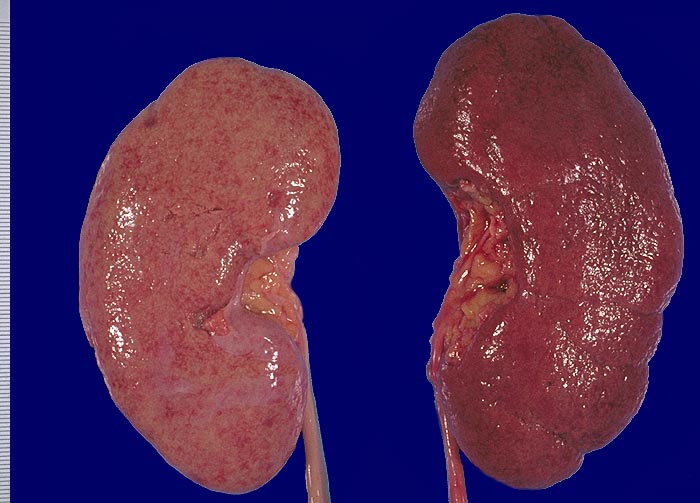

Im allgemeinen ist die Niere infolge von Glomerulumhypertrophie und Tubulushyperplasie vergrössert und derb, die Oberfläche ist granuliert. Bei schwerer Atherosklerose und fortgeschrittener Niereninsuffizienz kann die Niere auch normal gross oder verkleinert sein. Die Kombination von nodulärer Glomerulosklerose, hyalinen Schlingenkappen (=Proteinthromben in den Glomerulumschlingen (> 1916)) oder Kapseltropfen (> 1907) und Arteriolosklerose in Vas afferens und efferens ist beweisend für eine diabetische Nephropathie. Jede einzelne Läsion für sich genommen ist aber unspezifisch. Eine noduläre Glomerulosklerose kann auch vorkommen bei membranoproliferativer Glomerulonephritis (> 2652), Leichtkettenglomerulopathie oder Amyloidose (> 2019). Der nodulären Glomerulosklerose geht bei Diabetikern eine diffuse Glomerulosklerose (> 1906) voraus. Dabei zeigen die glomerulären Basalmembranen und das Mesangium eine progrediente gleichförmige Verbreiterung. Bei der nodulären und diffusen Glomerulosklerose handelt es sich aber wahrscheinlich um zwei pathogenetisch unterschiedliche, sich überlagernde Krankheitsbilder. Typisch bei Diabetikern ist im Unterschied zur arteriellen Hypertonie die Arteriolosklerose von Vas afferens und efferens (> 1911) und oft auch der Vasa recta. Intrarenale Arterien können eine Atherosklerose mit Atheromen zeigen. Subendotheliale Proteinablagerungen teilweise mit Verschluss der Glomerulumschlingen (Schlingenkappen) und knotige Proteinablagerungen in der Bowman'schen Kapselbasalmebran (Kapseltropfen) gehören zu den sogenannten exsudativen Läsionen (> 1919) (> 1920) der diabetischen Nephropathie und führen zu Synechien sowie zur globalen Glomerulosklerose. Gleichzeitig mit den Glomerulumveränderungen treten tubuläre Basalmembranverbreiterungen auf, später eine Tubulusatrophie und interstitielle Fibrose mit Begleitentzündung. Auch die Basalmembranen der peritubulären Kapillaren sind verdickt.

Normalbefund

Morphologie